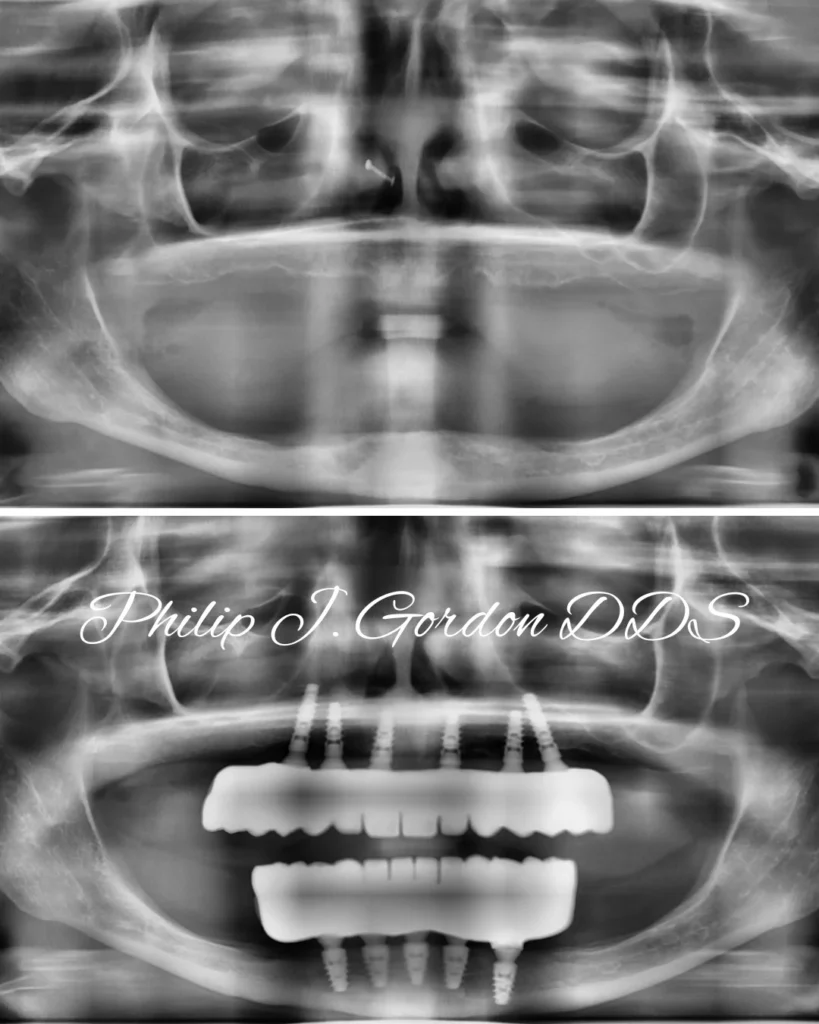

Here’s a direct look at a patient’s journey, showcasing the dramatic difference a full-arch restoration can make:

This is more than just a new smile; it’s a renewed ability to eat, speak, and live fully. Our patients from Kansas City and surrounding communities like Leawood and Overland Park experience life-changing results every day.

The X-ray above powerfully illustrates the precision of dental implant placement and the robust foundation they create for a full arch of new teeth. This advanced visualization is a cornerstone of our success.